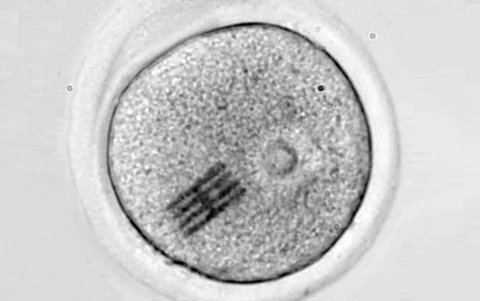

Interior del óvulo

El diminuto chip, cuya forma recuerda a los paneles solares de la estación espacial internacional, aunque es más fino que un coronavirus, en el interior de un óvulo.

El chip es un sensor minúsculo que mide apenas 22 por 10,5 micrometros y tiene un grosor de 25 nanometros, es decir, una longitud tres veces más pequeña que el diámetro de un cabello humano y un grosor tres veces menor que el del virus SARS-CoV-2.

El chip mide apenas 22 por 10,5 micrometros y tiene un grosor de 25 nanometros, es decir, una longitud tres veces más pequeña que el diámetro de un cabello humano.